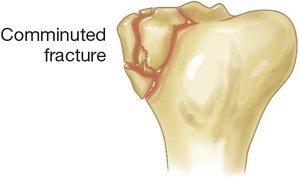

Comminuted Fracture | Bone shattered into multiple pieces |